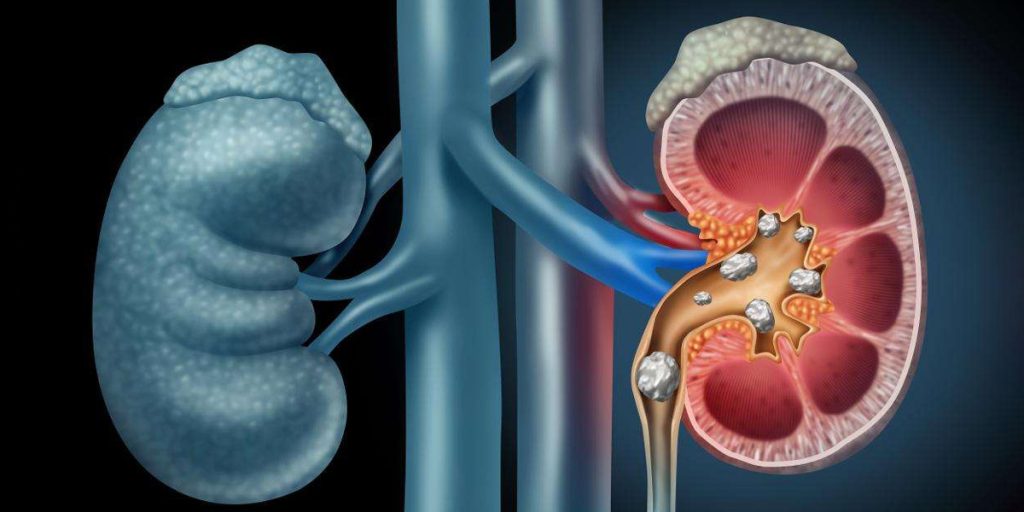

La formación de cálculos en la vejiga puede ocurrir por vaciamiento incompleto, infecciones o presencia de cuerpos extraños. Estas piedras pueden causar dolor, sangrado, dificultad para orinar y riesgo de infecciones. Su tratamiento varía desde manejo conservador hasta procedimientos endoscópicos.